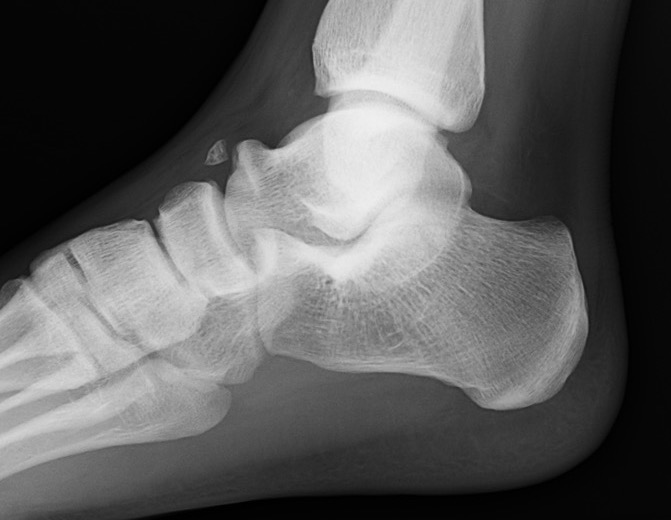

Xray

| Talar beaking | C Sign | Harris axial view | Ball and socket ankle joint |

|---|---|---|---|

| Traction spur due to increased stress | Medial outline talar dome and posterior sustenaculum tali |

40 degree axial view Ski jump view Visualize middle facet |

Secondary to rigid subtalar joint Develops to allow inversion / eversion |

Talar beaking with C sign

CT

TC coalition middle facet

Complete synostosis of the medial TC joint with OA of the posterior subtalar joint